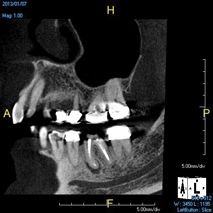

(4.) In a CBCT image axial view, the MB1 and MB2 canals are readily visible in tooth No. 14, and in the coronal view, these two separate canals can be seen to merge into a single apical opening.

Figure 4

(5.) In a CBCT image axial view, the MB1 and MB2 canals are readily visible in tooth No. 14, and in the coronal view, these two separate canals can be seen to merge into a single apical opening.

Figure 5